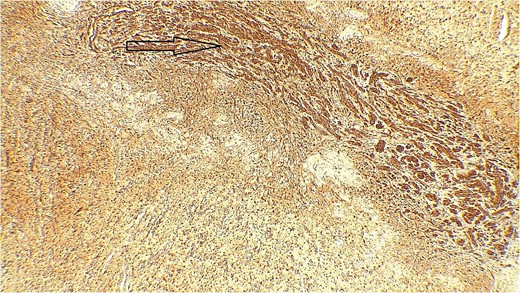

The result of the fine needle aspiration (FNAC) was a bland-looking spindle cell lesion, suggestive of a neural origin lesion like schwannoma. The patient was positioned in a supine position after she received general anesthesia. The face was turned to the opposite side of the tumor with a slight extension of the neck. An S-shaped incision was carried out in the front of the ear to the ear lobule, then it curved around the mastoid process posteriorly near the mastoid process and swung to the upper cervical creases smoothly. The cervical-facial skin flap was elevated with dissection to expose the tumor adequately, and then a traction suture was placed over the earlobe to widen the visual field for the operator. Dissection was carried out until the tumor was completely exposed, showing a smooth, ovoid, and whitish mass along the main trunk of the facial nerve (Fig. 1). The nerve was seen entering and exiting the posterior aspect of the mass on both sides. The layers over the mass were opened, and the mass was enucleated, leaving a flattened nerve posteriorly. No parotid gland excision was carried out. The postoperative histopathological examination revealed neurofibroma (Fig. 2) with a positive expression for S100 immune stain (Fig. 3). Postoperatively, the patient developed moderate (grade III) facial nerve dysfunction with obvious but not disfiguring deformity of the right side of the face, likely due to the pressure effect of the mass or traction during the operation. Two months after the operation, the facial nerve status improved to grade one, and after 4 months, she developed full recovery of facial nerve function.

Bland-looking cellular spindle cells (dark arrow) infiltrating into adjacent fibrofatty tissue (yellow arrow), Hematoxylin, and Eosin stain. Microscopic power 4 × 10.